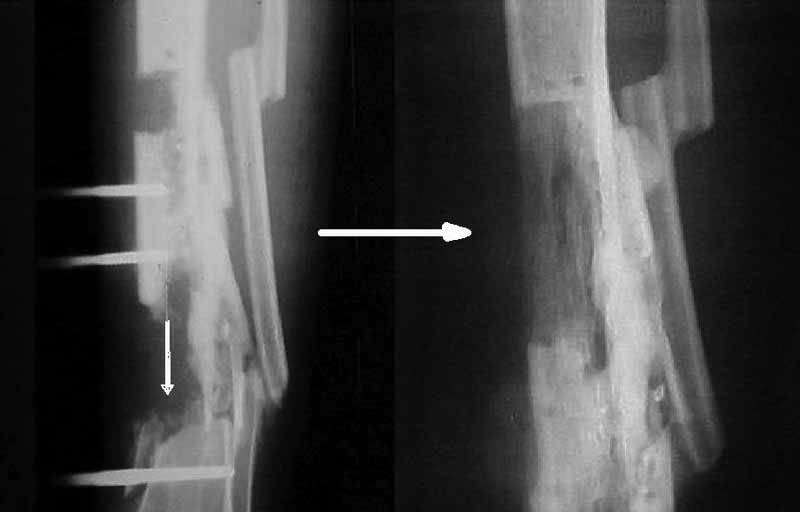

Я бы сделал пластику мягких тканей (торакодорзальный лоскут совместно с микрохирургами или пластику латеральной головкой икроножной мышцы) и выполнил бы краевой отщеп большеберцовой кости для его дистракции аппаратом в проксимальном направлении (рис. 1 – пример применения отщепа (авторство не мое), рис. 2 – схема предлагаемого варианта замещения дефекта кости).

2. Хотелось бы увидеть снимки раннего периода, лучше после травмы, а также КТ. Интересует целостность плато б/б кости. По представленным

снимкам возникает подозрение, что наружный мыщелок отделен. Или это так кажется?